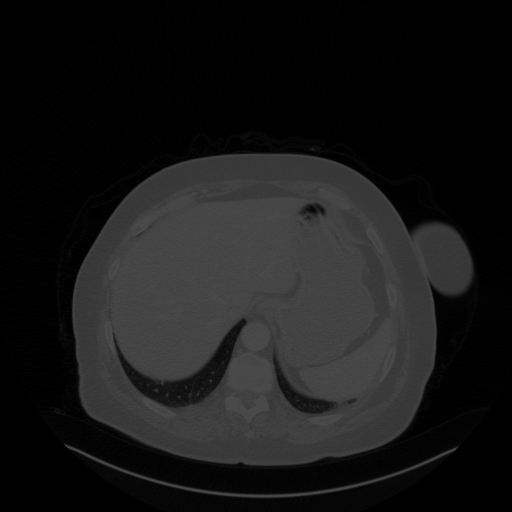

Image Grid

4Γ—3 grid: Rows show different image types (Original NATIVE, Reconstructed NATIVE, Original VENOUS, Generated VENOUS), Columns show windowing techniques (No Window, Lung Window, Mediastinum Window)

Lung window (WL -600, WW 1500 β†’ Low βˆ’1350, High +150)

Reconstructed NATIVE CT scan (cycle consistency)

Original VENOUS CT scan

Generated VENOUS CT scan (A→B translation)